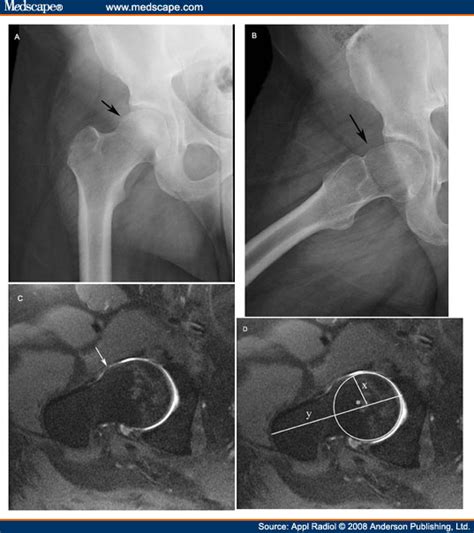

• Cam Deformity: The radiologist will assess the shape of the femoral head to see if there’s a bump or aspherical shape. This is often measured using angles like the alpha angle. An alpha angle greater than 50-55 degrees can indicate a cam deformity.

• Pincer Overcoverage: The acetabulum is evaluated to determine if it’s covering too much of the femoral head. This can be assessed by measuring the lateral center-edge angle. An angle greater than 40 degrees may suggest pincer impingement.

• Labral Tears: MRI is excellent at detecting tears in the labrum. These tears can appear as irregularities or fluid within the labrum. The location and extent of the tear are important for planning treatment.

• Cartilage Damage: The radiologist will look for thinning, irregularities, or defects in the cartilage. Cartilage damage is a sign of more advanced hip impingement and can indicate the need for more aggressive treatment.